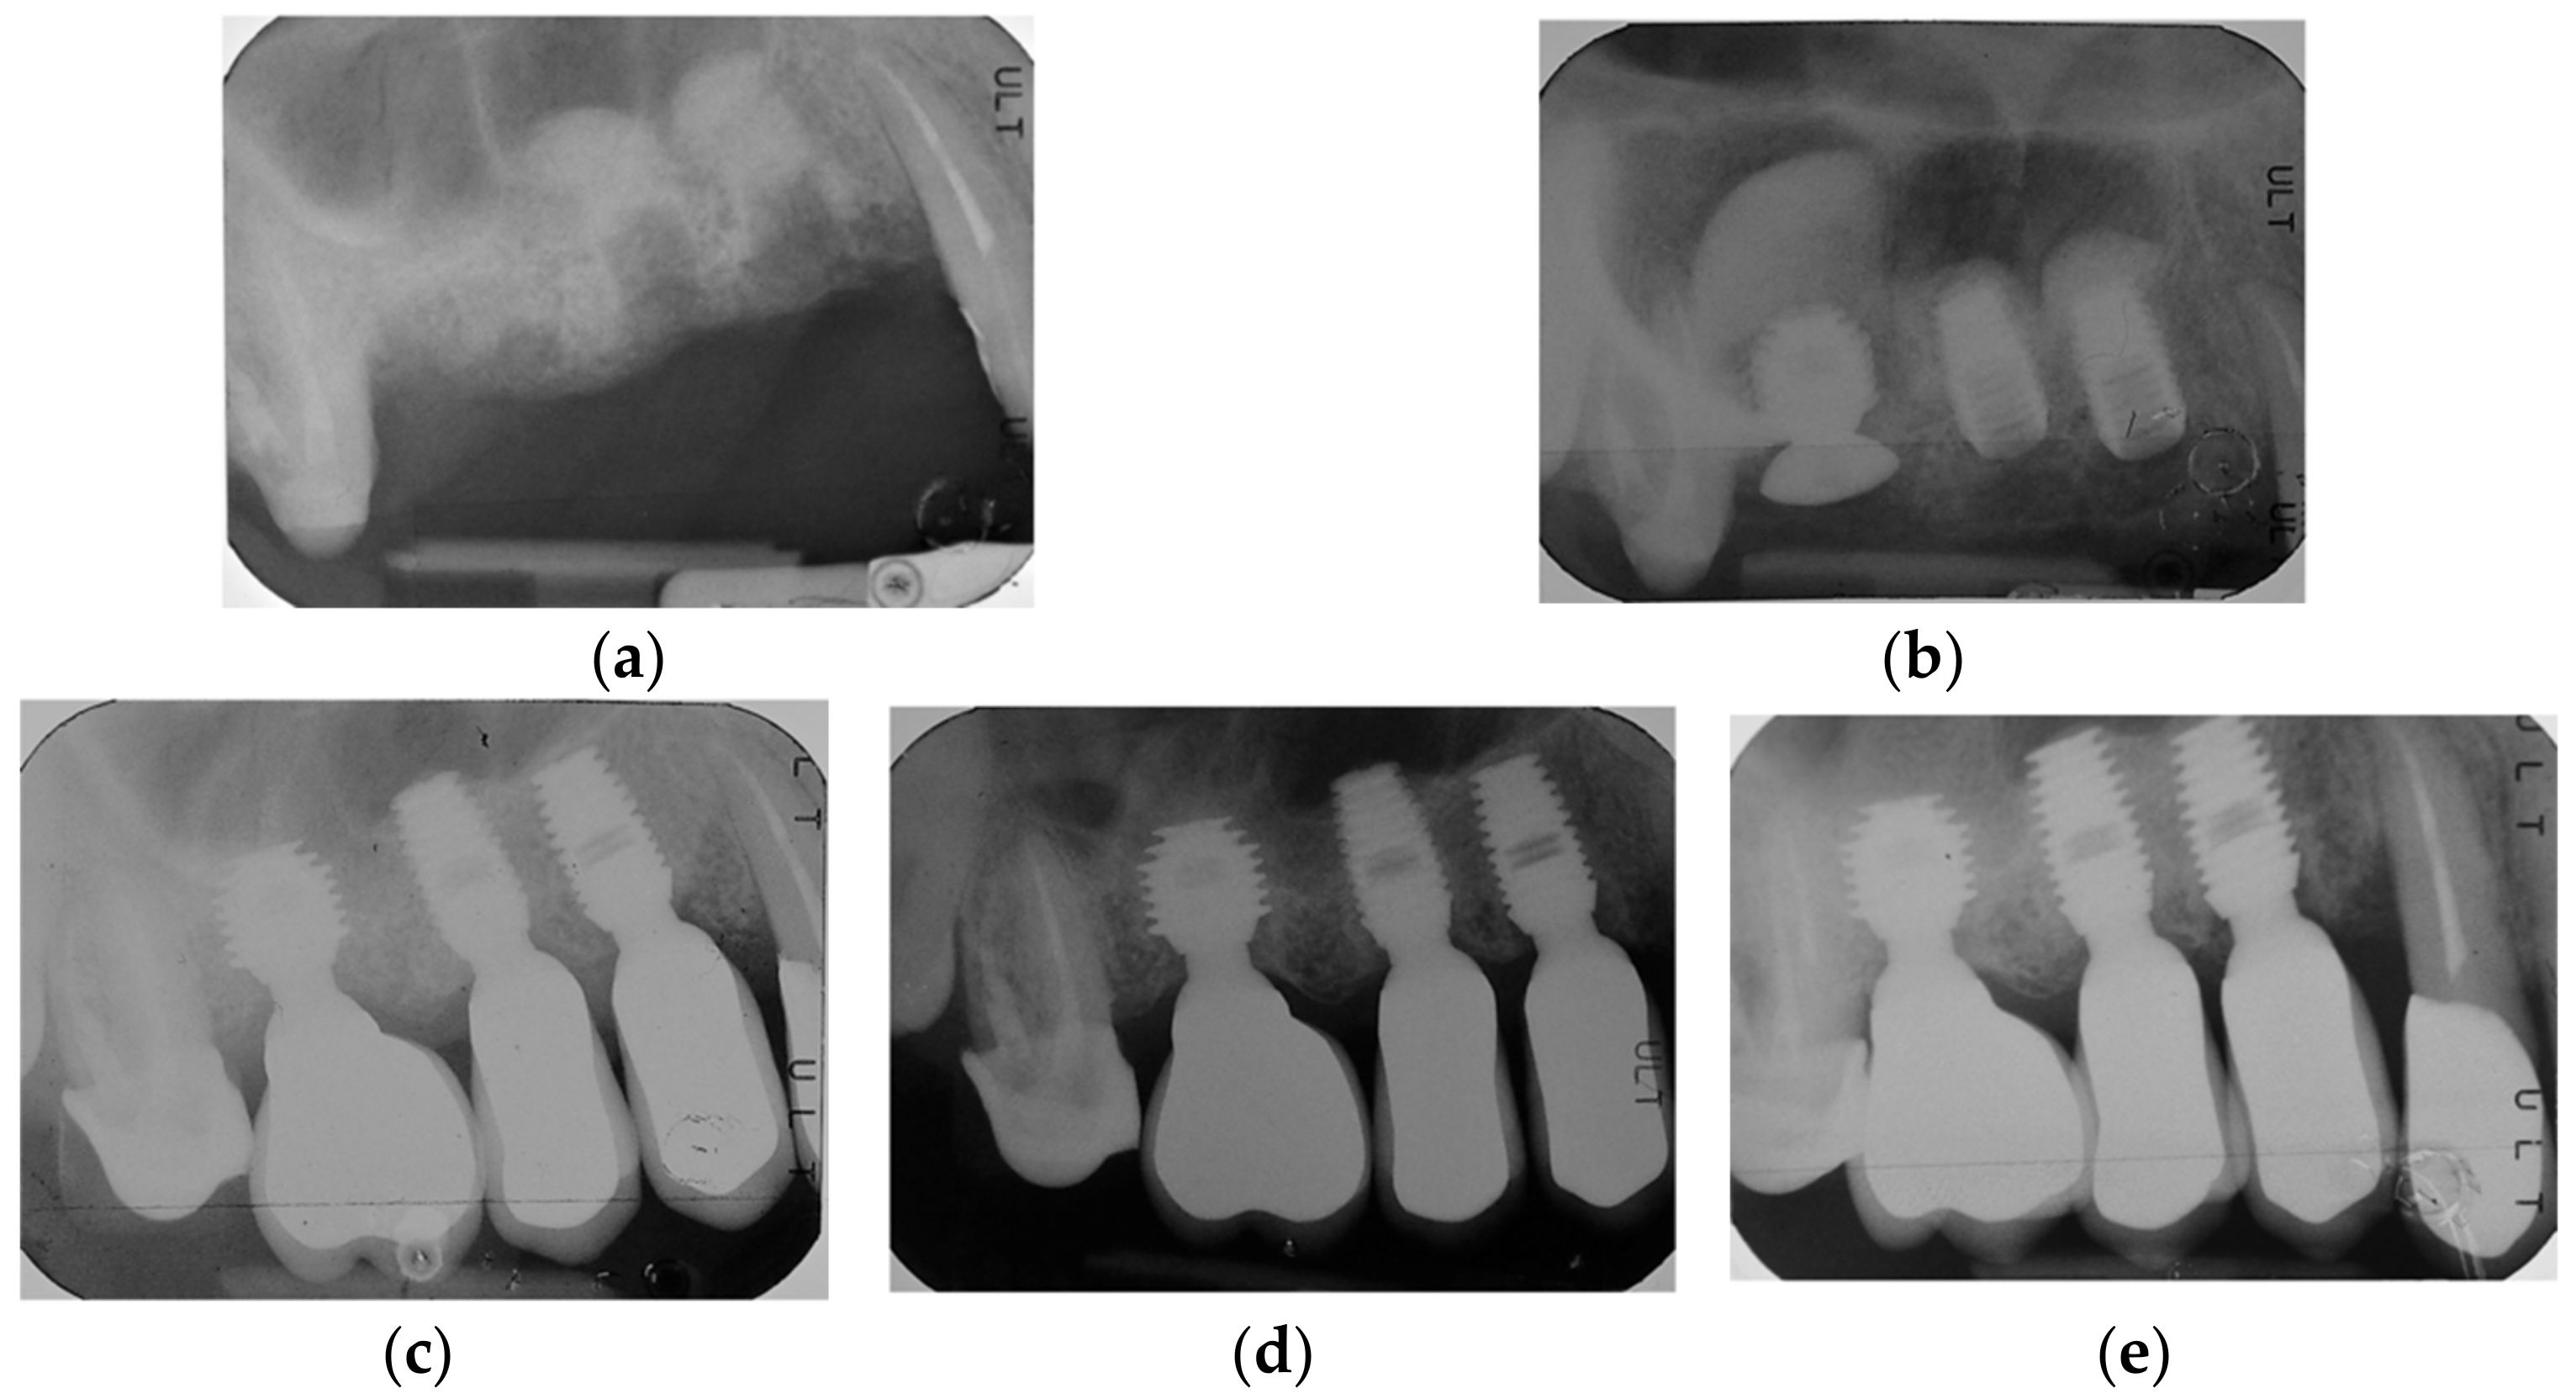

2.2. Surgical Protocol

2.3. Prosthetic Protocol and Follow-Up Evaluation

3.4. Patients’ Level of Satisfaction